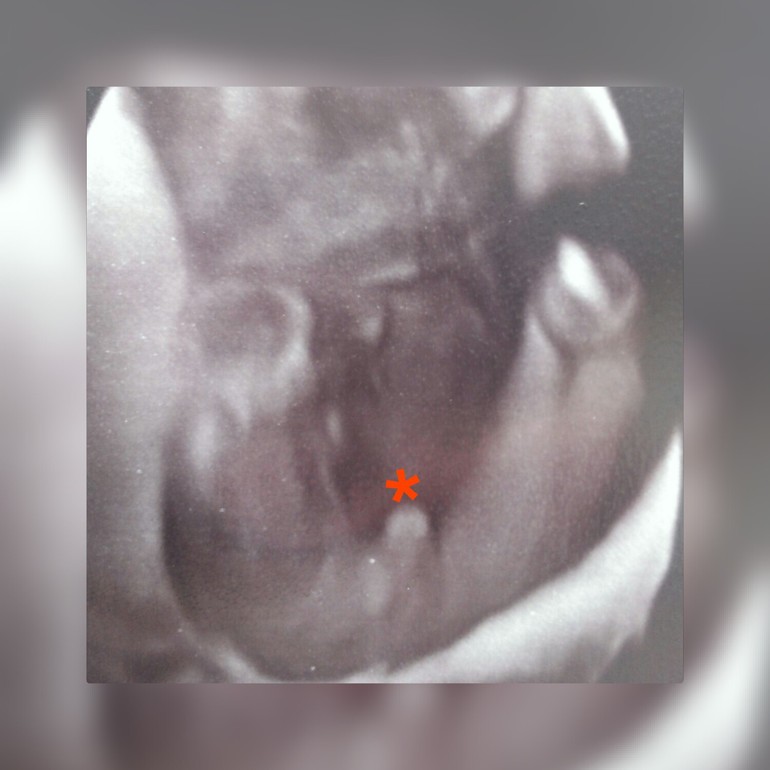

Наше узи на 17,6 недельке)

УЗИ, КТГ, доплерКак давно я уже не писала сюда )с последней б. прошло уже больше 2 лет)))) и вот она незапланированная беременность)муж конечно в шоке и категорически против....но я оставила ,раз всевышний дал значит так надо))) у нас три девочки и я очень хотела мальчика) на 12 недельке сказали что похож на мальчика)))а вчера направили на узи так как постоянно давление падало (((( сказали что с малышом всё хорошо и.... Что это мальчик)))))

но так как муж всё таки не верил что будет мальчик ,для него сделали специальное фото))))))))))сестрички очень довольны ,старшая дочка была со мной на узи и видела своего братика на втором экране)))))